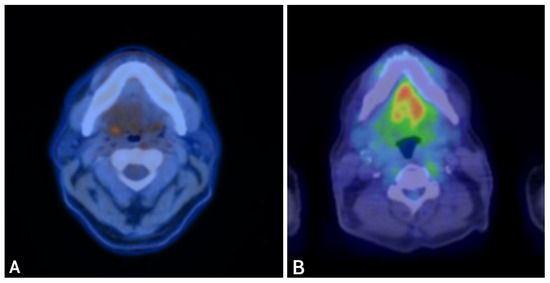

Three months later, surveillance imaging showed local recurrence. Repeat endoscopic resection demonstrated discordant margins, which persisted after a second re-resection. Pembrolizumab was started, but after three doses PET-CT showed progression with FDG-avid sinonasal, orbital, vomer, right cervical nodal, and pulmonary involvement (Figure 4A–C).

Figure 4.

PET-CT imaging before and after fluoropyrimidine-based therapy in Case 3. Legend: Representative PET-CT images show FDG-avid disease at multiple sites before therapy and the response after fluoropyrimidine-based treatment. Pre-treatment (Panels (A–C)): FDG-avid disease involving the left maxillary sinus mass (A), right cervical lymph nodes (B), and right pulmonary nodules (C). Post-treatment (Panels (D–F)): Restaging PET-CT images demonstrate remarkable partial metabolic response at all previously involved sites, with reduction in FDG uptake and lesion size (D–F).

The patient was referred for a second opinion to the Head and Neck Oncology Clinic at our institution. He reported persistent sinonasal pressure requiring Norco every five hours and diplopia interfering with daily activities. Given strong CDX2 expression consistent with enteric differentiation, FOLFOXIRI chemotherapy was initiated.

After three months, restaging PET-CT showed markedly decreased sinonasal uptake, improved nodal disease, and near-complete resolution of pulmonary nodules (Figure 4D–F). Clinically, the patient experienced significant pain relief (2/10 from 7/10) and complete resolution of diplopia.